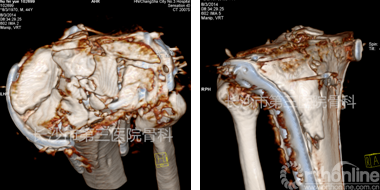

手术当日,该订制钢板通过后内侧入路成功完成了对胫骨平台后、内侧柱的复位固定,较以往明显减少软组织剥离的同时缩短了手术时间,节约了患者的治疗费用,获得了满意的治疗效果。

术后CT复查

该例手术为湖南省首例利用3D打印技术结合数字化个性钢板完成的复杂骨科手术,标志着长沙市三医院骨科在骨科治疗数字化进程方面迈上了一个新的台阶。